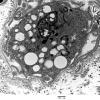

PERIPHERAL NEUROPATHY

4 AXONAL DEGENERATION

4 Macrophages (2)